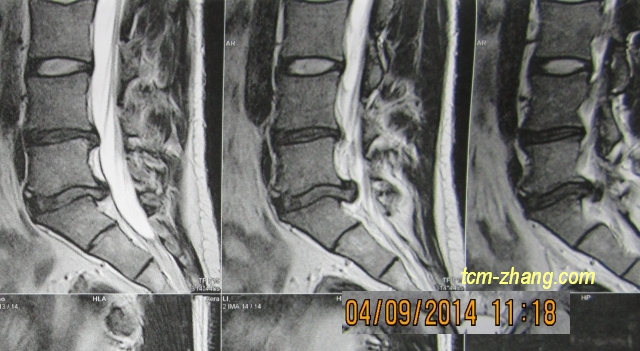

Ich hatte in 2014 einen Bandscheibenvorfall, wo ich gut trainiert und gut gedehnt war. Die Schulmedizin konnte mir damals leider nichtmehr helfen. Ich bekam 6 Wochen lang Opiate, ziemlich starke, trotzdem konnte so gut wie nicht aufstehen, bin ich 6 wochenlang nur gelegen, bekam dazwischen in die Klinik lange Injektion direkt in die Wirbelsäule gespritzt, mit Schmerzmittel und Kortison, und auch das nicht geholfen.

Und nach 6 Wochen stand die Operation im Raum. Das ist einzige Möglichkeit die Schulmedizin noch bitten konnte.

Ich bekam damals, Gott sein Dank, die Empfehlung für Herrn Zhang und bin dann zu ihn gegangen. Und bereits nach einer Sitzung war eine deutliche Besserung spürbar. Ich konnte wieder aufstehen, ich konnte gehen, ich konnte stehen. Und nach 2-3 Sitzungen bei ihm waren die Schmerzen so gut wie verschwunden, eigentlich komplett verschwunden. Die Opiate konnte ich absetzen, und die Schmerzen waren weg.

Seit dem bin ich beschwerdefrei. Ab und zu wenn die Gewitterung(das Wetter) sehr kalt ist, und leicht Anfang zu ziehen, vielleicht einmal in Jahr oder alle zwei Jahren, wenn ich verspüre gehe ich wieder zu Herrn Zhang. Ich bin ihn sehr sehr dankbar, und das nicht war die Operation bewahr hatte und mein Rücken stabil ist.